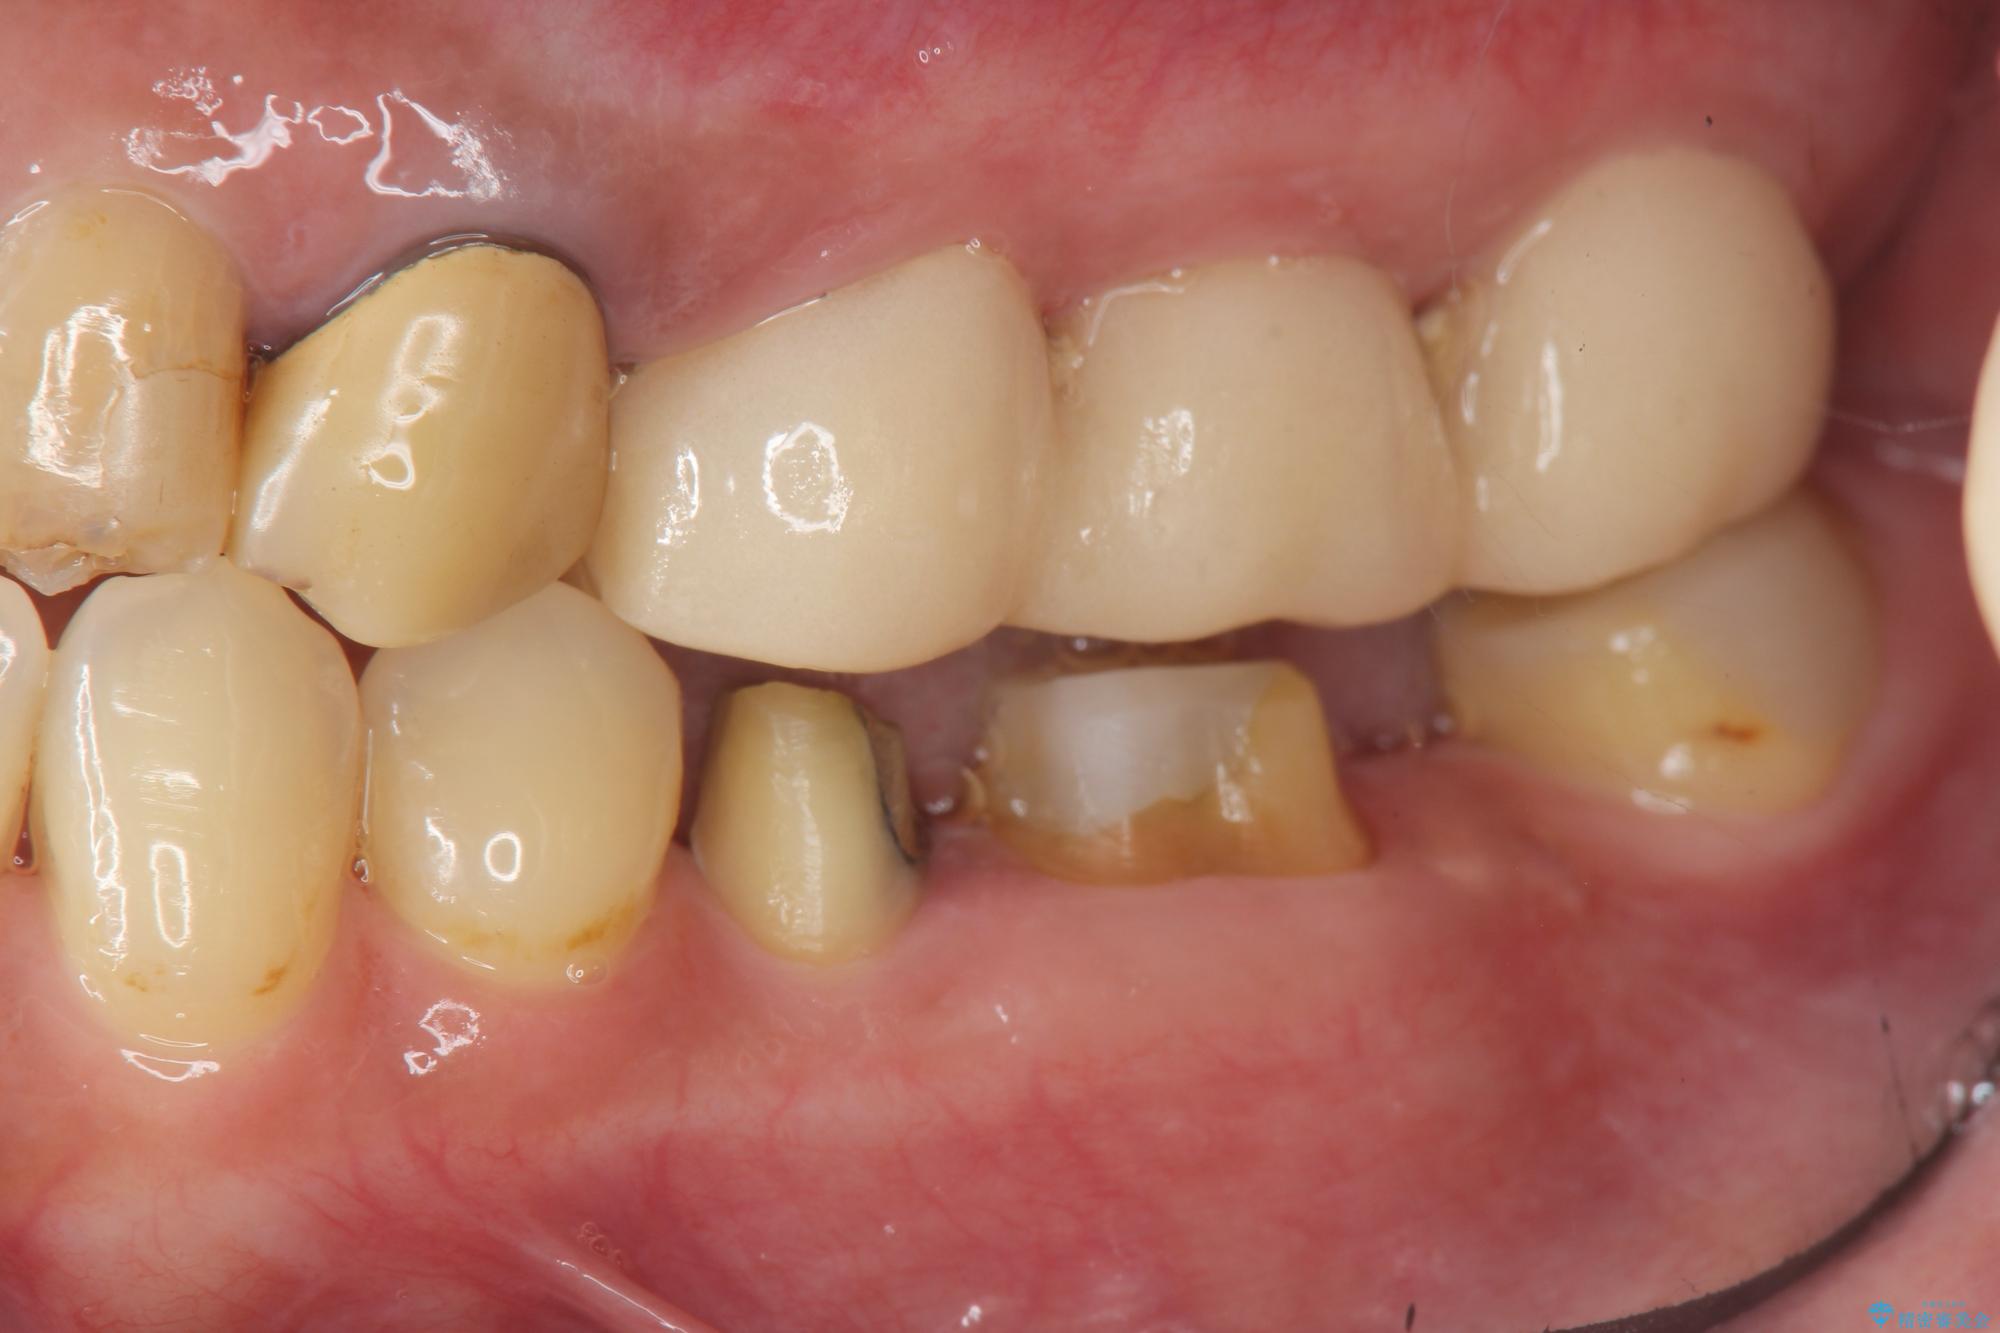

抜歯後、インプラントを用いて咬合機能を回復すると共に周囲に強固な角化歯肉を移植することによりより長期にわたり安定したインプラント周囲環境となるよう治療を計画します。

インプラント周囲の角化歯肉が存在することにより、歯ブラシがしやすくなりインプラントにトラブルが起きる確率を減らしより長期的な予後を望むことができます。